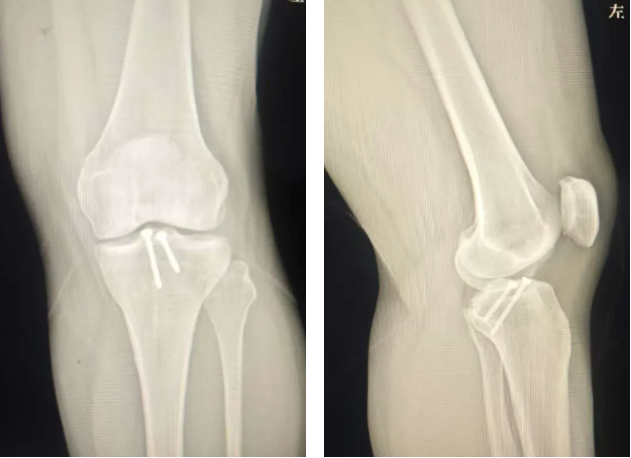

术前X线检查

45岁的朱女士被膝盖不稳折磨了15年,近两个月更是频繁出现关节交锁。当多家医院因内固定取出难度高而拒绝手术时,朱女士经多方打听来到郑州大学五附院骨科一病区,找到徐明杰主任就医。徐明杰主任与张鹏飞医师为其查体后发现患者抽屉试验阳性,考虑患者膝关节不适不仅和内固定有关,而且可能和交叉韧带损伤有关,复查MRI检查后果然发现前交叉韧带断裂。